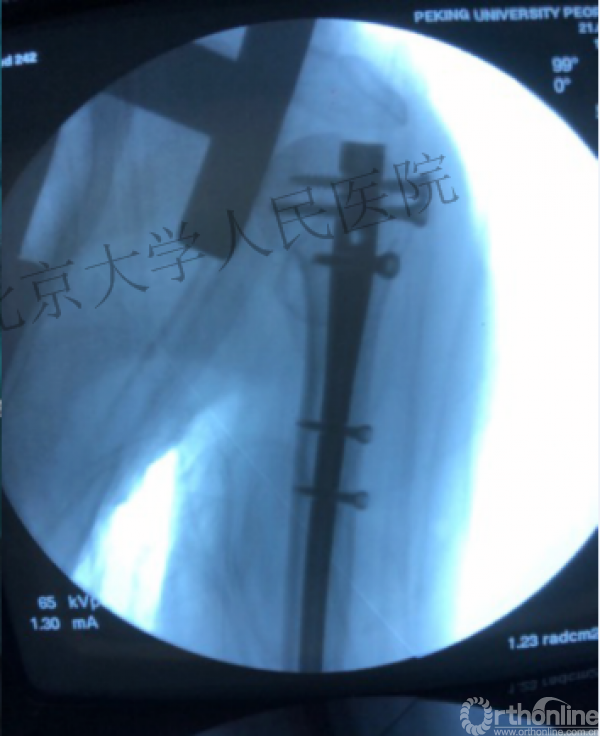

1.体位与C臂机的应用

透视肱骨头正位、侧位确定进针点

术中片